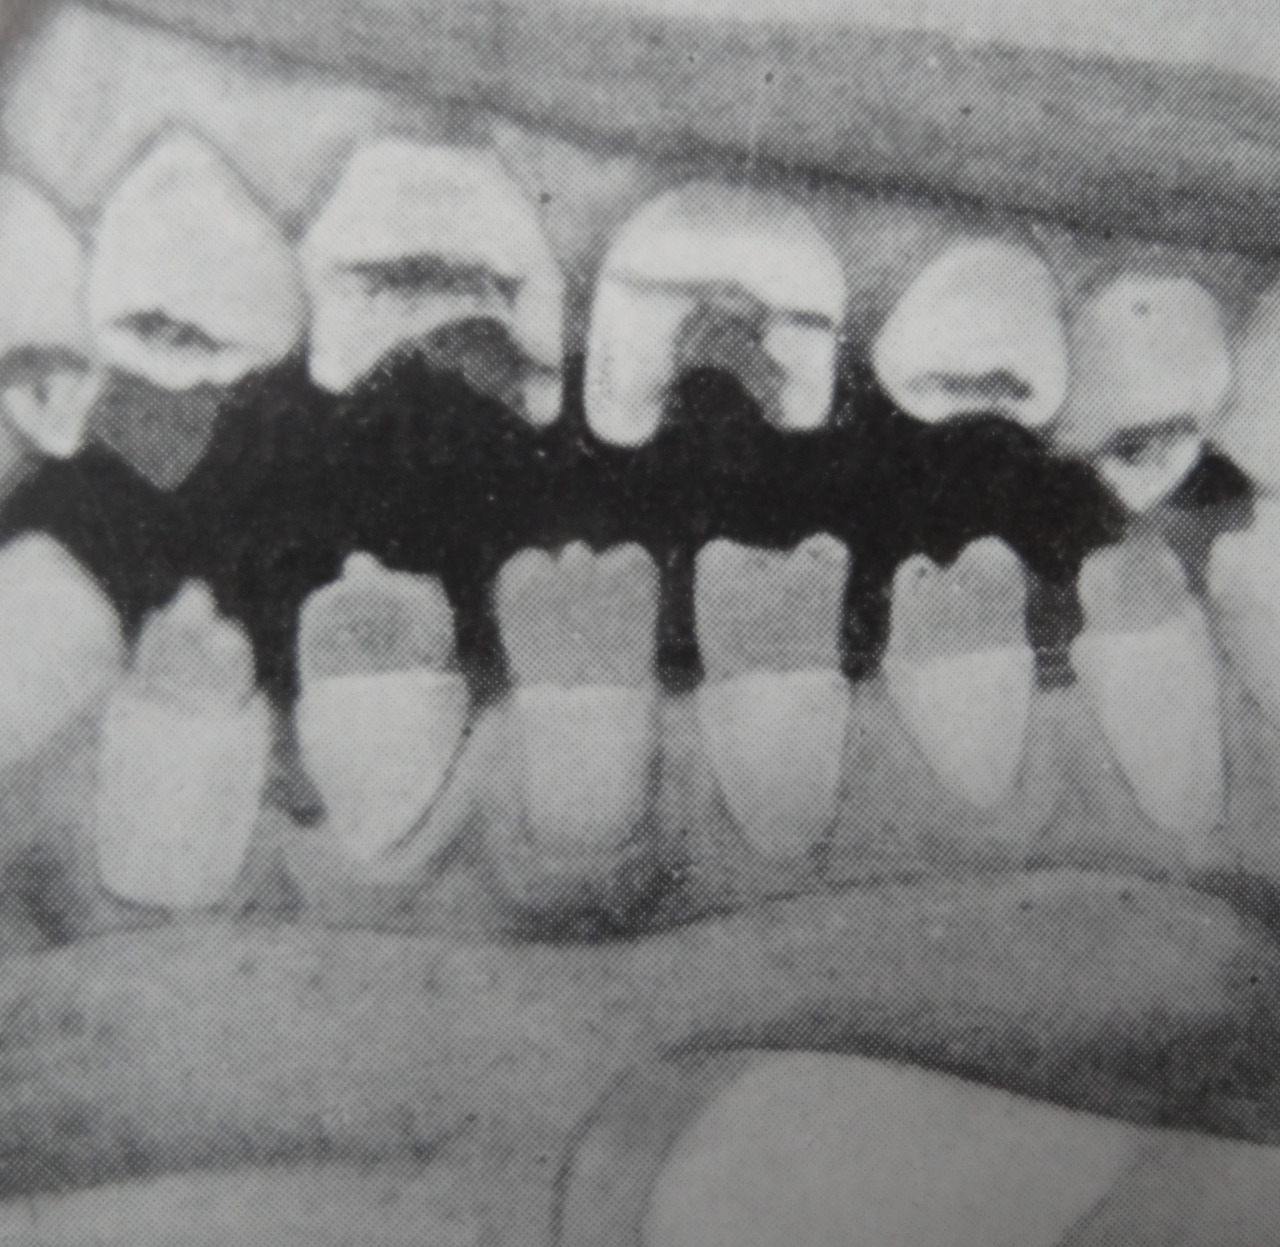

La forme congénitale tardive se manifeste après l’âge de 2 ans par l’apparition de gommes syphilitiques au niveau du ­palais ou de la cloison nasale, de lésions périostées entraînant une déformation « en lame de sabre » des tibias (fig. 2) et de saillies des os frontal et pariétaux. Par ailleurs, peuvent survenir une kératite interstitielle d’évolution insidieuse et indolore, une atrophie optique responsable de cécité, une surdité (lésion du nerf auditif) et des malformations au niveau du maxillaire et des dents (fig. 3). Ces atteintes sont ­malheureusement irréversibles.

Le diagnostic de syphilis congénitale ­tardive doit être évoqué devant la présence de symptômes cliniques et la positivité des tests sérologiques (ELISA, VDRL, RPR) et l’association de kératite, de lésions dentaires et de surdité (triade de Hutchinson). Un bilan sanguin, neuro­logique, oph­talmologique et radiologique est indispensable.